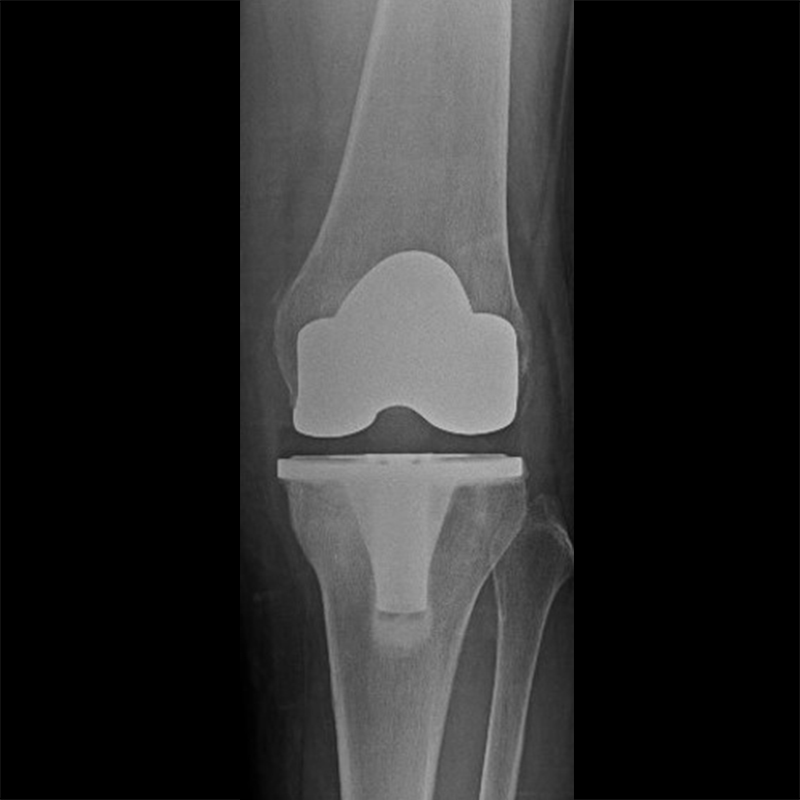

外院失敗本院再置換 首頁 案例分享 膝關節手術 外院失敗本院再置換 蕭女士 69歲 術前 術後 81歲 林女士 術前 術後 蕭女士 69歲 術前 術後 鄒女士 69歲 術前 術後 李女士 74歲 術前 術後 吳女士 71歲 術前 術後 謝女士 65歲 術前 術後